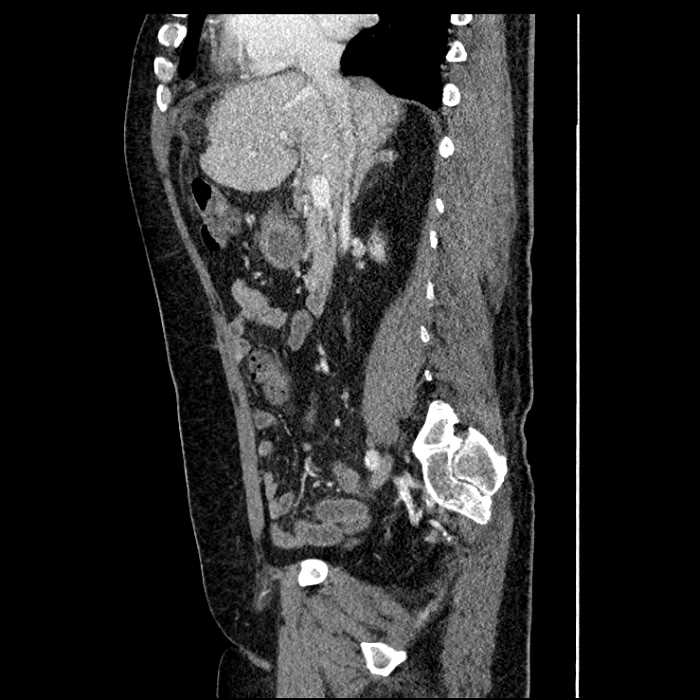

Age: 63

Sex: Male

Indication: Abdominal pain

• Large fluid density structure in hepatic segments 7 and 8 measuring 10 x 7 x 7 cm with internal septation and circumferential ill-defined low density compatible with edema

• Peripherally enhancing subcapsular collections along the anterior margin of the left hepatic lobe measuring 3 x 1 cm and 2 x 1 cm

• Clearly marginated fluid density structure in segment 7 and several other scattered tiny hypodensities, which likely represent cysts

• Hepatic abscess

Acute sigmoid diverticulitis complicated by a small contained perforation and a large abscess in the right hepatic lobe. Additional small subcapsular abscesses along the anterior margin of the left hepatic lobe.

• The classic CT imaging appearance is a double target sign with internal low density surrounded by an internal enhancing rim (capsule) and a low density external rim (edema)

• Abscesses may be unilocular or multilocular

• Gas is present in a minority of cases

Hepatic abscess showing the double target sign with low density internally surrounded by a thin inner enhancing rim (red arrow) and ill-defined outer low density rim (yellow arrow). Blue arrow indicates an internal septation. Red arrows: additional smaller subcapsular abscesses. Red arrow: focal contained perforation associated with diverticulitis.